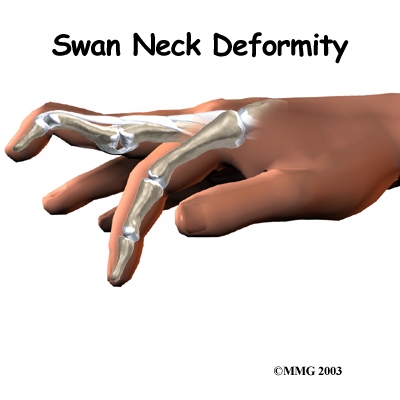

Both rheumatoid arthritis and osteoarthritis can affect the IP joints of the fingers. The IP joints may begin to flex (bend) or hyperextend (over straighten), causing characteristic finger deformities. occurs when the middle finger joint (the PIP joint) becomes loose and hyperextended, while the DIP joint becomes flexed. When the PIP joint flexes and the DIP joint extends, a forms.

Related Document: Combined Therapy Specialties Guide to Swan Neck Deformity of the Finger